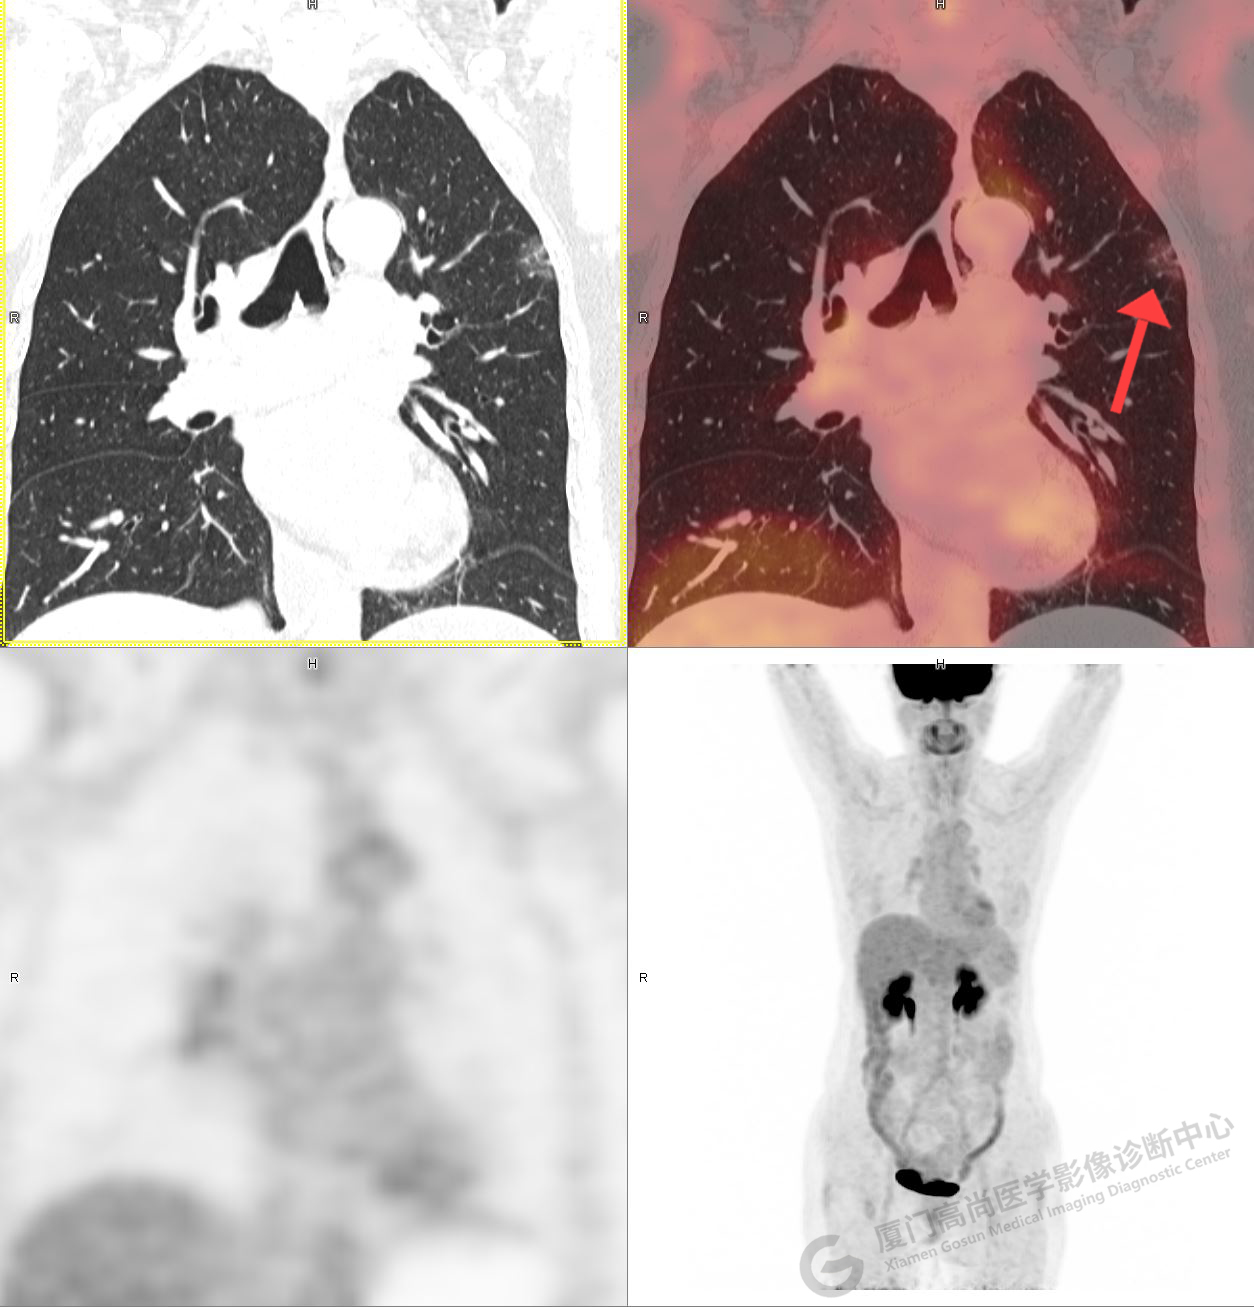

PET/CT影像圖

圖1

圖2

PET/CT示:右肺上葉尖段混雜密度結(jié)節(jié),代謝不高,考慮為早期肺癌(微浸潤腺癌),建議病理學(xué)檢查。

病理證實(shí)是肺腺癌。